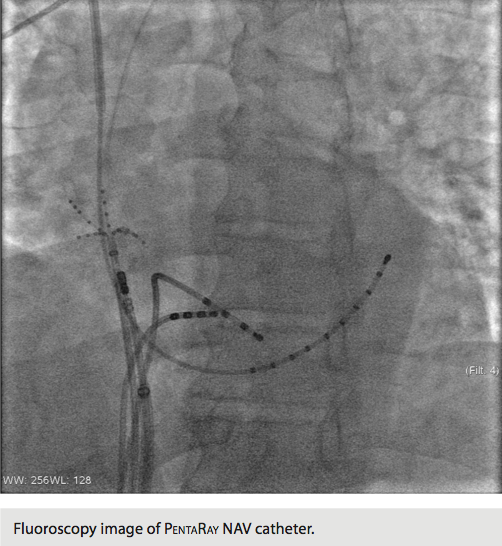

The PentaRay NAV is recommended for use in cases of atrial tachycardia, ventricular tachycardia, and complex fractionated electrograms in atrial fibrillation. The intent of this catheter is to provide high-resolution maps with the fewest moves necessary to create them. It has a five-branched star design, and these branches are soft and very flexible in order to decrease risk of traumatic injury to the endocardium. Signal resolution has also been improved. In addition, pacing can be performed from any electrode.

There are currently four PentaRay NAV catheters available for use. The catheters are available in both F and D curves. The shaft is a 7 French (Fr) and requires an 8 Fr sheath with a saline flush for the inner lumen of the sheath. Spacing consists of 4-4-4 and 2-6-2. There are 20 poles on each catheter divided among the five branches. The required interface cable to the PIU was already in our stock, as the PentaRay NAV utilizes the same cable as the original Lasso catheter (not the ECO). The C-Code for this catheter is C1732.

At this time, there are no recommendations as to which catheter spacing is best for certain patient conditions. Utilization depends on physician preference. We chose to utilize the D Curve catheter with the 4-4-4 spacing. However, it should be noted that although there are 20 poles on the catheter, it is not linear like a 10- or 20-pole catheter. Not every pole produces an intracardiac signal. The catheter with the 4-4-4 spacing has 15 intracardiac signals for viewing, while the 2-6-2 spacing has 10.

Using the Carto 3 three-dimensional electroanatomical mapping system and the Biosense Webster MEM, we performed fast activation mapping of the entire right atrium. We took approximately 400 points with the PentaRay NAV catheter in less than 10 minutes. Review of these points demonstrated that the earliest atrial electrogram (when compared to CS poles 8-7) was seen at the lateral tricuspid annulus.

Next, with pacing in the high right atrium, we were able to induce a different atrial tachycardia, which appeared to be emanating from the posterolateral tricuspid annulus, approximately 4 cm away from the site of the original tachycardia. Again, using the PentaRay NAV catheter, we remapped this tachycardia in the right atrium. The area of earliest atrial activation on this occasion was at the posterolateral tricuspid annulus, and atrial electrograms achieved at this site preceded the coronary sinus reference electrode by 87 msec. They also preceded the onset of the P-wave by 40 msec.

Our initial impression of this new technology was very favorable. The PentaRay NAV catheter facilitated an accurate and fast construction of the right atrial map. The initial map guided us to the tricuspid annulus and quickly identified it as the source of the arrhythmia. During this case, an additional atrial tachycardia was noted and two separate maps were needed. Previously, mapping of multiple atrial tachycardias was extremely time-consuming because of the need for multiple maps. The PentaRay NAV catheter allowed us to take 400 points in less than 10 minutes and formulate a single map, when other technology would have taken 45 to 60 minutes to achieve the same result. In summation, two atrial tachycardia maps of at least 400 points each were constructed in less than 20 minutes during this case.